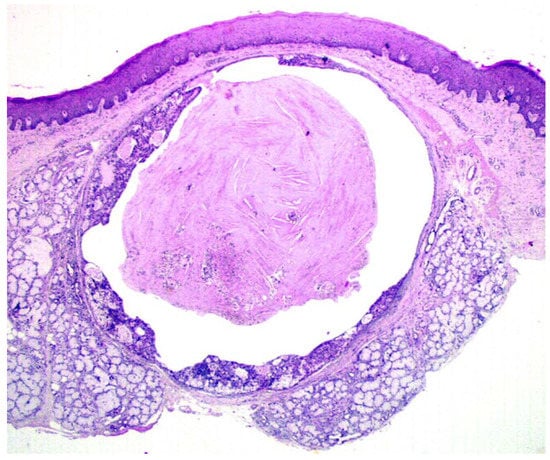

Gross examination disclosed well defined cystic lesions, and microscopically, at scanning magnification, a single cystic space was detectable in all samples, showing parietal proliferation of clusters of epithelial cells with a focal cribriform growth pattern (Figure 2). The central part of the cyst was filled with proteinaceous material and cholesterol crystals, while a distinct and complete rim of collagenous stroma separated the cyst from the surface epithelium and from adjacent lobules of mucous salivary glands. The clusters of epithelial proliferation (Figure 3) were composed by small columnar and intermediate cells, cells with prominent cytoplasmic clearing and marginated nuclei, scattered flat to polygonal cells showing epidermoid differentiation and a reduced number of large mucous-producing cells with multivacuolated cytoplasm. The latter were better highlighted with Alcian Blue (Figure 4) and Mucicarmine stains and also showed PAS-positivity, which was partly abolished after diastase treatment. Occasionally, smaller cystic spaces with cribriform appearance were evident within the neoplastic epithelial clusters, which were lined by cuboidal to columnar cells. Nuclear pleomorphism was minimal, as was mitotic activity (<1/10 high power fields), while inflammatory infiltration, necrosis and perineural invasion were undetectable; additionally, tumor-free margins (> 1 mm) were assessed in all cases. Patients had been followed-up for a minimum of five years (range: 62–120 mo.; median: 68 mo.) and had remained without evidence of disease up to January 2019.

Figure 2. Under scanning magnification, the tumor was composed of a single cystic space, partly filled with proteinaceous material and cholesterol crystals, and showed parietal growth of epithelial cells and complete peripheral demarcation by fibrous connective tissue. (H&E, x1).